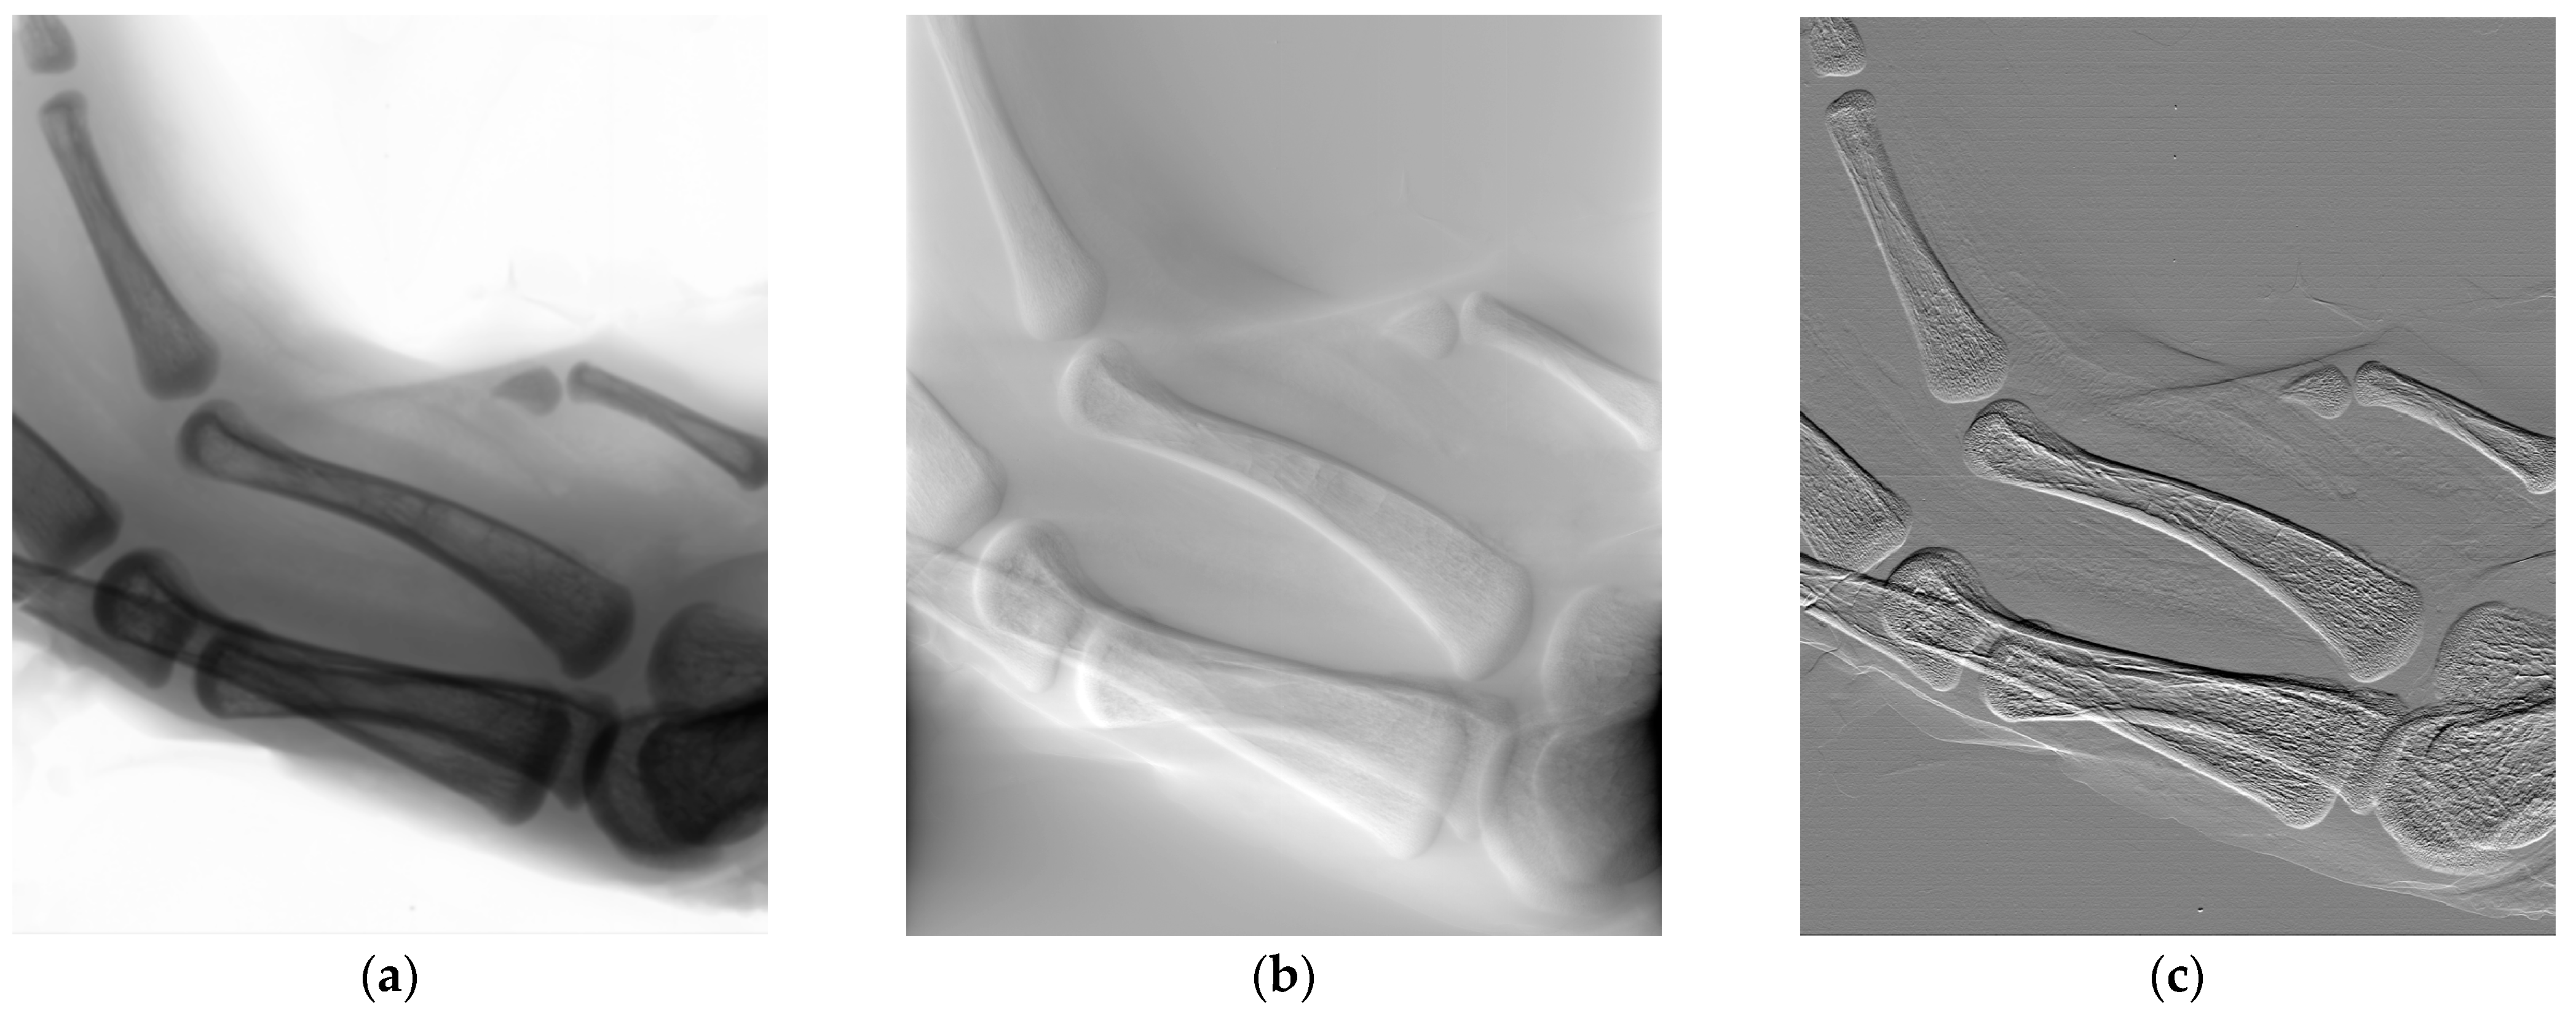

3.3. Micrography